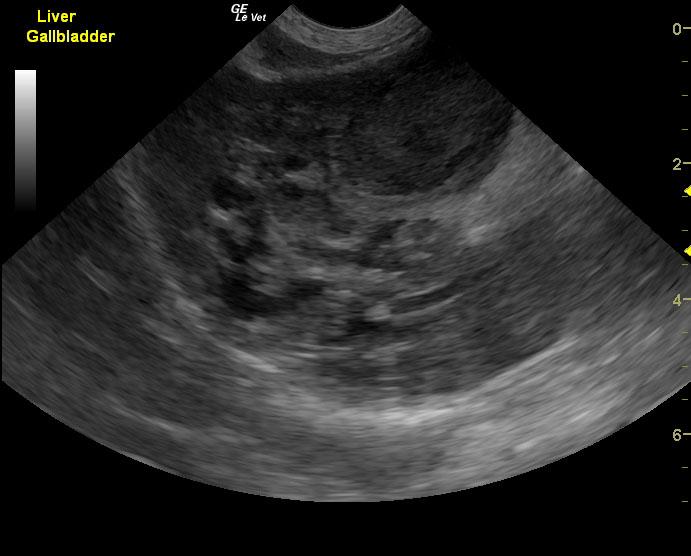

A 10-year-old, SF DSH cat was presented for acute onset vomiting and dehydration. Abnormalities on physical examination were icterus and dehydration. Pyuria with low urine SG was present on urinalysis. Urine culture was negative for bacterial growth after 24hrs. CBC and serum biochemistry showed marked leukocytosis with left shift and azotemia. Diffuse intestinal ileus was evident on survey radiographs.